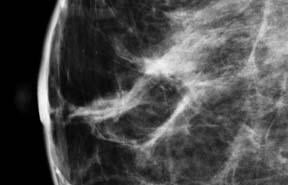

April 3, 2012 — Breast cancer patients whose treatment includes radiation therapy are at higher risk of complications after implant-based breast reconstruction, reports a study in the April issue of Plastic and Reconstructive Surgery, the medical journal of the American Society of Plastic Surgeons (ASPS).

The researchers looked at how radiation affected complication rates in 194 breast cancer patients undergoing two-stage, implant-based breast reconstruction after mastectomy. About 12 percent of reconstructions were done on women undergoing radiation therapy before mastectomy, and six percent in women who received radiation after mastectomy.

The results confirmed an increased complication rate in women undergoing radiation therapy, whether before or after mastectomy. In both radiation groups, the complication rate during reconstruction was over 40 percent, compared to 14 percent for women who did not receive radiation.

Types of complications also differed between groups. Twenty-two percent of women undergoing radiation had problems related to wound healing—a well-known consequence of radiation damage to tissues. In contrast, wound complications occurred in less than two percent of women not treated with radiation, and only in smokers. Smoking is also a known risk factor for wound-healing problems.

Problems related to the tissue expander were the second most common complication in the radiation groups, with a rate of 19 percent. The overall risk of major complications requiring additional surgery was about six times higher in women receiving radiation therapy, after adjustment for other factors. For smokers, the risk of major complications was more than three times higher.

The rate of complications leading to repeat surgery for women who have undergone radiation therapy appears "prohibitively high," Lin and co-authors concluded. They also noted that however, 80 percent of women with radiation therapy—even with major complications—had successful breast reconstruction surgery.

Radiation causes tissue damage that increases the risk of complications of breast reconstruction, among other types of surgery. In general, breast reconstruction using the patient's own (autogenous) tissue is preferred for patients who have undergone radiation therapy. However, this type of reconstruction requires more extensive surgery and longer recovery time.

Implant-based reconstruction is much quicker, but requires the use of radiation-damaged tissues. Because it is very effective in reducing the risk of recurrence, radiation therapy has become an increasingly common part of combination therapy approaches to breast cancer.